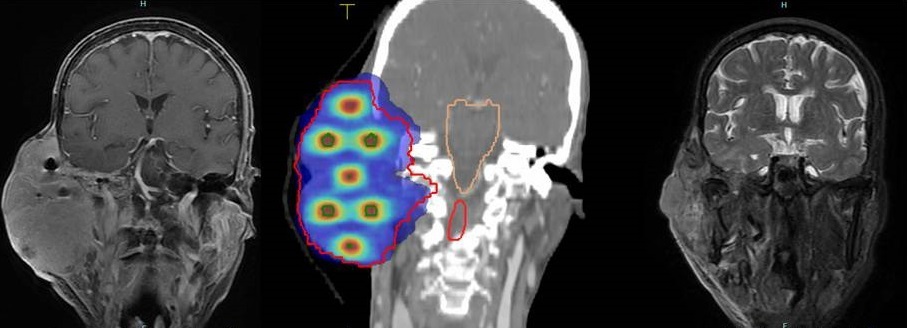

放疗前后影像图(左边为入院时影像,右边为放疗结束后1个月复查影像,中间为晶格放疗剂量分布图)

面对这种棘手的情况,吴媛团队综合评估后,决定启用医院新引入的晶格放疗——通过高精度立体定向技术,在肿瘤内部构建三维“晶格状”剂量分布,通过高剂量“峰区”和低剂量“谷区”交替分布的独特剂量场,实现杀灭癌细胞、最大限度保护周围正常组织的目标。2025年11月,患者先后接受了两个疗程的晶格放疗。

经过治疗,奇迹发生了,患者巨大肿块肉眼可见地迅速消退,疼痛症状开始缓解、溃烂面开始愈合,原本因肿瘤压迫导致的各种症状也得到明显改善。放疗结束后1个月复查,影像显示肿瘤明显缩小;3个月后复查,肿瘤基本消退,疗效评估基本达到完全缓解,后续仅需口服免疫药物维持。患者治疗期间无明显不良反应,生活质量得到了保障。

吴媛介绍,晶格放疗是全球新兴的一种空间分割放疗技术,能将肿瘤划分为数以千计的微观治疗单元,利用3D晶格矩阵实现剂量分布的精准调控,打破了传统放疗只能对肿瘤全区域进行同等剂量均匀照射的局限。其在肿瘤内部构建离散的高剂量“靶点”,用极高剂量射线直接摧毁大部分的癌细胞,“靶点”周边区域则使用低剂量射线,降低对重要器官的伤害,同时还能激活人体免疫应答,引发全身性抗肿瘤免疫反应,逐渐将剩余的癌细胞一并歼灭。